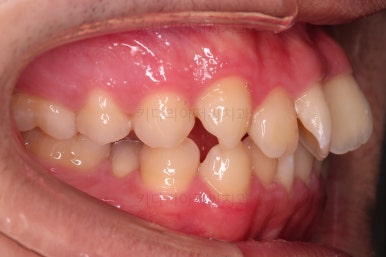

초진 시, 입안의 모습입니다.

치아를 모두 담기에 골격이 매우 작았어요.

이런 경우 치열이 ㅃ뚤어지거나 입이 튀어나오거나 뻐드렁니가 되거나 특정 치아가 묻혀버리거나 맨 뒤치아가 마치 사랑니처럼 올라오지 못한다거나 등등의 문제가 생기는데요.

이번 환자분은 전반적으로 삐뚠 상황이었어요.

앞니도 대칭적으로 삐뚤어져 흔히 나비치아라고 하는 형태로 보이고, 아랫니들은 U자 아치의 형태가 찌그러져 있네요.

당연히 교합도 맞지 않고요.